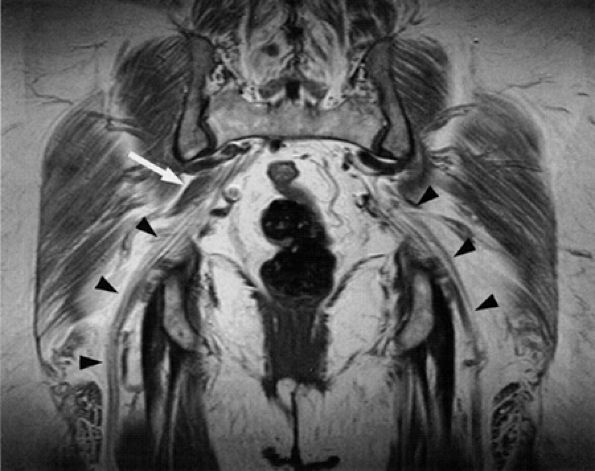

FIGURE 6.7 ● Coronal T1-weighted image of the sciatic nerve demonstrating the normal fascicular pattern of both sciatic nerves (arrowheads). A slip of the right piriformis muscle is noted (arrow).

FIGURE 6.8 ● Normal sciatic nerve. (A) An axial PD-weighted image at the upper thigh demonstrates a normal ovoid-shaped sciatic nerve (black arrow) anterior to the gluteus maximus muscle (GM), highlighted by the fat. Note the proximity of the nerve to the hamstring tendons (white arrows). (B) An axial PD-weighted image at the middle thigh depicts the tibial (arrowhead) and smaller peroneal (arrow) divisions of the sciatic nerve in a common sheath before they diverge in the proximal knee.

|